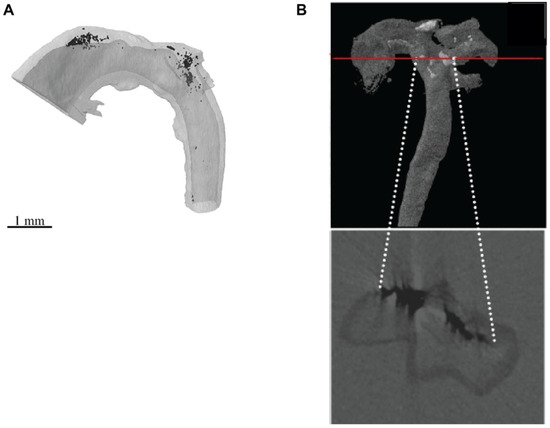

To date, only a handful of studies have utilized laboratory µCT sources to analyze vascular calcification in animal models [73,94,95,96,122]. Arterial medial calcification has been quantified using µCT in formalin-fixed, corn oil immersed aortae from Enpp1−/− mice, achieving an isotropic voxel size of 7–10 µm (Figure 3A) [73,94]. However, a limitation of these studies was the inability to correlate the 3-D µCT data with subsequent 2-D histological analyses. To overcome this, Awan et al. [95,96] used paraffin-wax embedded aortas from atherosclerotic LDLR−/− mice to combine 3-D volumetric calcification analyses with 2-D histological analyses in the same arterial segment (Figure 3B). However, the low-resolution capabilities achieved (isotropic voxel size between 5 and 20 µm) in these studies prevented the visualization of the finer structures of the calcifications and the blood vessel wall extracellular matrix (ECM).

Figure 3.

µCT imaging of calcified mouse blood vessels. (A) A formalin-fixed, corn oil immersed aortae from the Enpp1−/− mouse model of arterial medial calcification was scanned by µCT using a voxel size of 10 µm, and the images reconstructed to form a 3-D imaged volume. X-ray dense calcifications (black) localized to the upper curvature of the ascending aorta and aortic arch. (B) A formalin-fixed, paraffin-wax embedded aorta from the LDLR−/− mouse model of atherosclerosis and arterial intimal calcification was scanned by µCT using a voxel size of 5.63 µm, and the images reconstructed to form a 3-D imaged volume. X-ray dense calcifications (black) are observed in a phase virtual slice from the 3-D imaged volume (indicated by the red line). (A) Reproduced from Reference [73] with permission. (B) Reproduced from Reference [95] with permission.